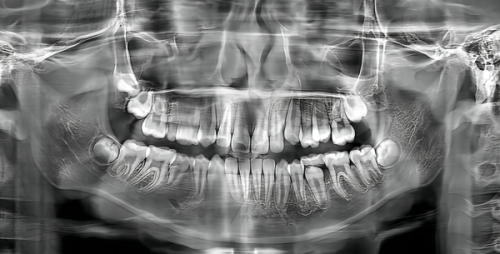

根管治疗(又称牙髓治疗)是治疗牙髓炎、坏死牙髓、根尖周围病变等常见可怕“牙痛症”的有效方式。医生会在局麻下打开患牙,移除感染的牙髓与根管内坏死组织,通过扩张、消毒、填充根管封闭感染途径。

① 口腔数字影像检查 ——精细判断牙髓感染范围及牙根结构